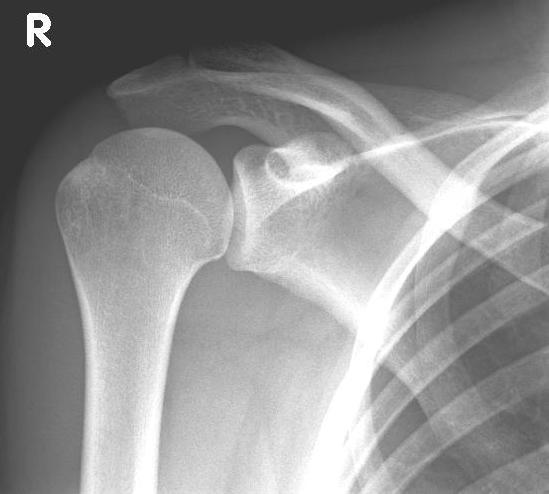

Conventional stem prostheses for omarthrosis and acetabular wear

right: anatomical shoulder prosthesis with glenoid replacement (Affinis type, Mathys company)